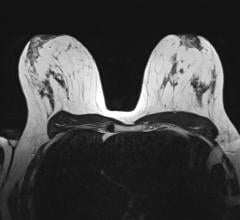

A novel imaging agent for PET, BMS747158 detects more ischemia than technetium SPECT/CT imaging.

In an effort to produce an affordable and accessible imaging agent for PET/CT, Lantheus Imaging is developing a fluorine 18-labeled (F-18) agent with a two hour half-life. The novel F-18 PET/CT tracer is designed for myocardial perfusion imaging (MPI). Like FDG, the new agent, called BMS747158, can be manufactured by a regional cyclotron and then shipped to several PET/CT imaging centers. According to Dr. Maddahi, this eliminates the need for an onsite cyclotron or generator.

The data from a Phase I study showed high myocardial uptake at rest that significantly increases with pharmacologically induced stress and a ratio of myocardial to background radioactivity that is favorable and improved over time. These findings suggest that BMS747158 has potential to be used as a myocardial perfusion PET/CT agent for patients both at rest and under stress.

In preliminary Phase 2 studies, Dr. Maddahi and his team have found BMS747158 detects more ischemia than Technetium SPECT/CT imaging.